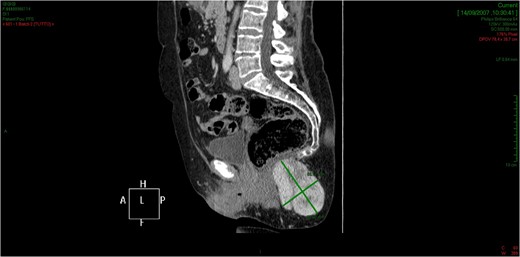

CT showed an hyperintense and inhomogeneous solid lesion taking up the right ischiorectal fossa (maximum diameter of about 10 cm), extended cranially until impressing the wall of the rectal ampulla, with no apparent infiltration (Figs 2 and 3). The lesion presented an intense contrast enhancement, sign of a rich vascularization (Fig. 4).

The CT scan demonstrates a solid neoformation in the right ischiorectal fossa.

The lesion extends cranially until impressing the wall of the rectal ampulla, with no apparent infiltration.